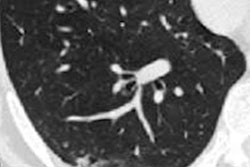

The researchers hypothesized that by proportionally reflecting lung parenchyma involvement, the quantity of opacities relative to the total lung volume may be predictive of survival and the need for more intensive medical care.

Two radiation oncologists with five- and 10-years' experience, respectively, performed contours of the lungs and the consolidations. The researchers then calculated the relative consolidation volume by dividing the volume of the lung consolidations by the total bilateral lung volume.